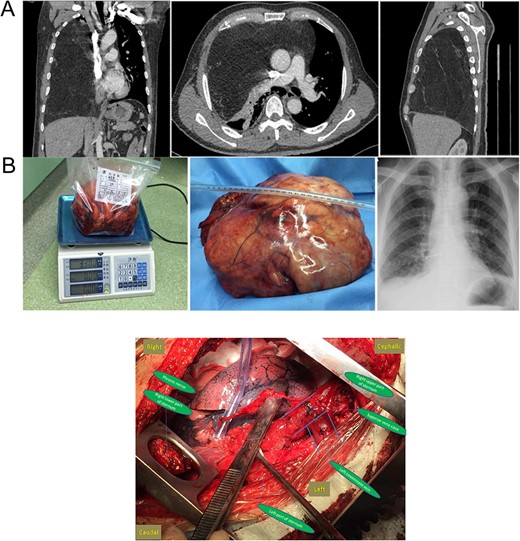

(A) Preoperative chest CT and (B) gross specimen and postoperative chest X-ray. Central Picture: “⊣ shape” incision and intraoperative surgical field after removing the giant mass.

Surgical exploration was performed first through a standard median sternotomy under general anesthesia. Dissection started from left phrenic nerve along the left innominate vein to superior vena cava. However, the giant tumor adhered severely to pericardium and the lower part of superior vena cava. Sternum transection plus a right fourth intercostal thoracotomy (‘⊣ shape incision’) was then added to guarantee a better exposure. Intraoperatively, a giant, well-capsulated yellow tumor without abundant blood supply was found, which also occupied the whole right thorax without invading the lung, chest wall, diaphragm and inferior vena cava. The main part of the tumor was smoothly removed from the right thorax after cutting off the mass along the pericardium, superior vena cava and pulmonary hilum. After careful dissection of adhesion, the rest of the tumor was gradually separated and successfully removed with partial pericardium (Central Picture). The atelectatic right lung obtained good reexpansion when both lungs were ventilated.

The gross size of the tumor was 27 cm × 20 cm × 15 cm, weigh ~3.3 kg. And it was covered with a capsule (Fig. 1B). The cut surface appeared lobulated in shape and was pale yellow in color. The final pathological diagnosis was a well-differentiated liposarcoma. The patient experienced an uneventful recovery. Postoperative chest radiography showed a normal right lung (Fig. 1B).